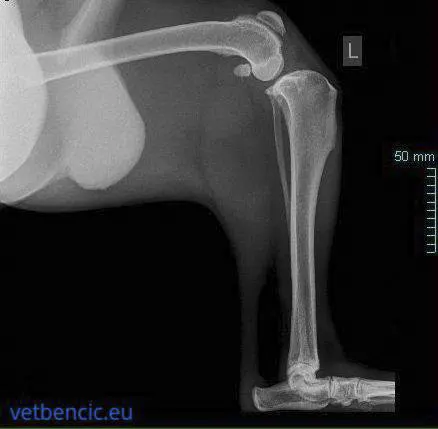

Nesrašteni ankonealni proces je stanje u kojem se koštani izdanak u laktu odvaja od ulne. Taj odvojeni fragment kosti uzrokuje bol i šepanje te doprinosi oštećenju zgloba lakta. Najčešće se dijagnosticira kod njemačkih ovčara i bernskih planinskih pasa. Posljedica je neusklađenosti lakta (nepodudarnost ulne ili sindrom kratke ulne).

Kod većine pasa ovo stanje uzrokuje jaku bol i očito šepanje.

Postizanje optimalnog ishoda ovisi o ranoj dijagnozi i liječenju.

RTG snimanje iz više projekcija, u sedaciji. U nekim slučajevima imamo suptilne promjene, kada ankonealna izraslina ostane blago priljubljena uz kost, pa je za dijagnostiku potreban CT. U pasa s nesjedinjenim ankonealnim izdancima najbolji se ishod postiže ranom kirurškom intervencijom: